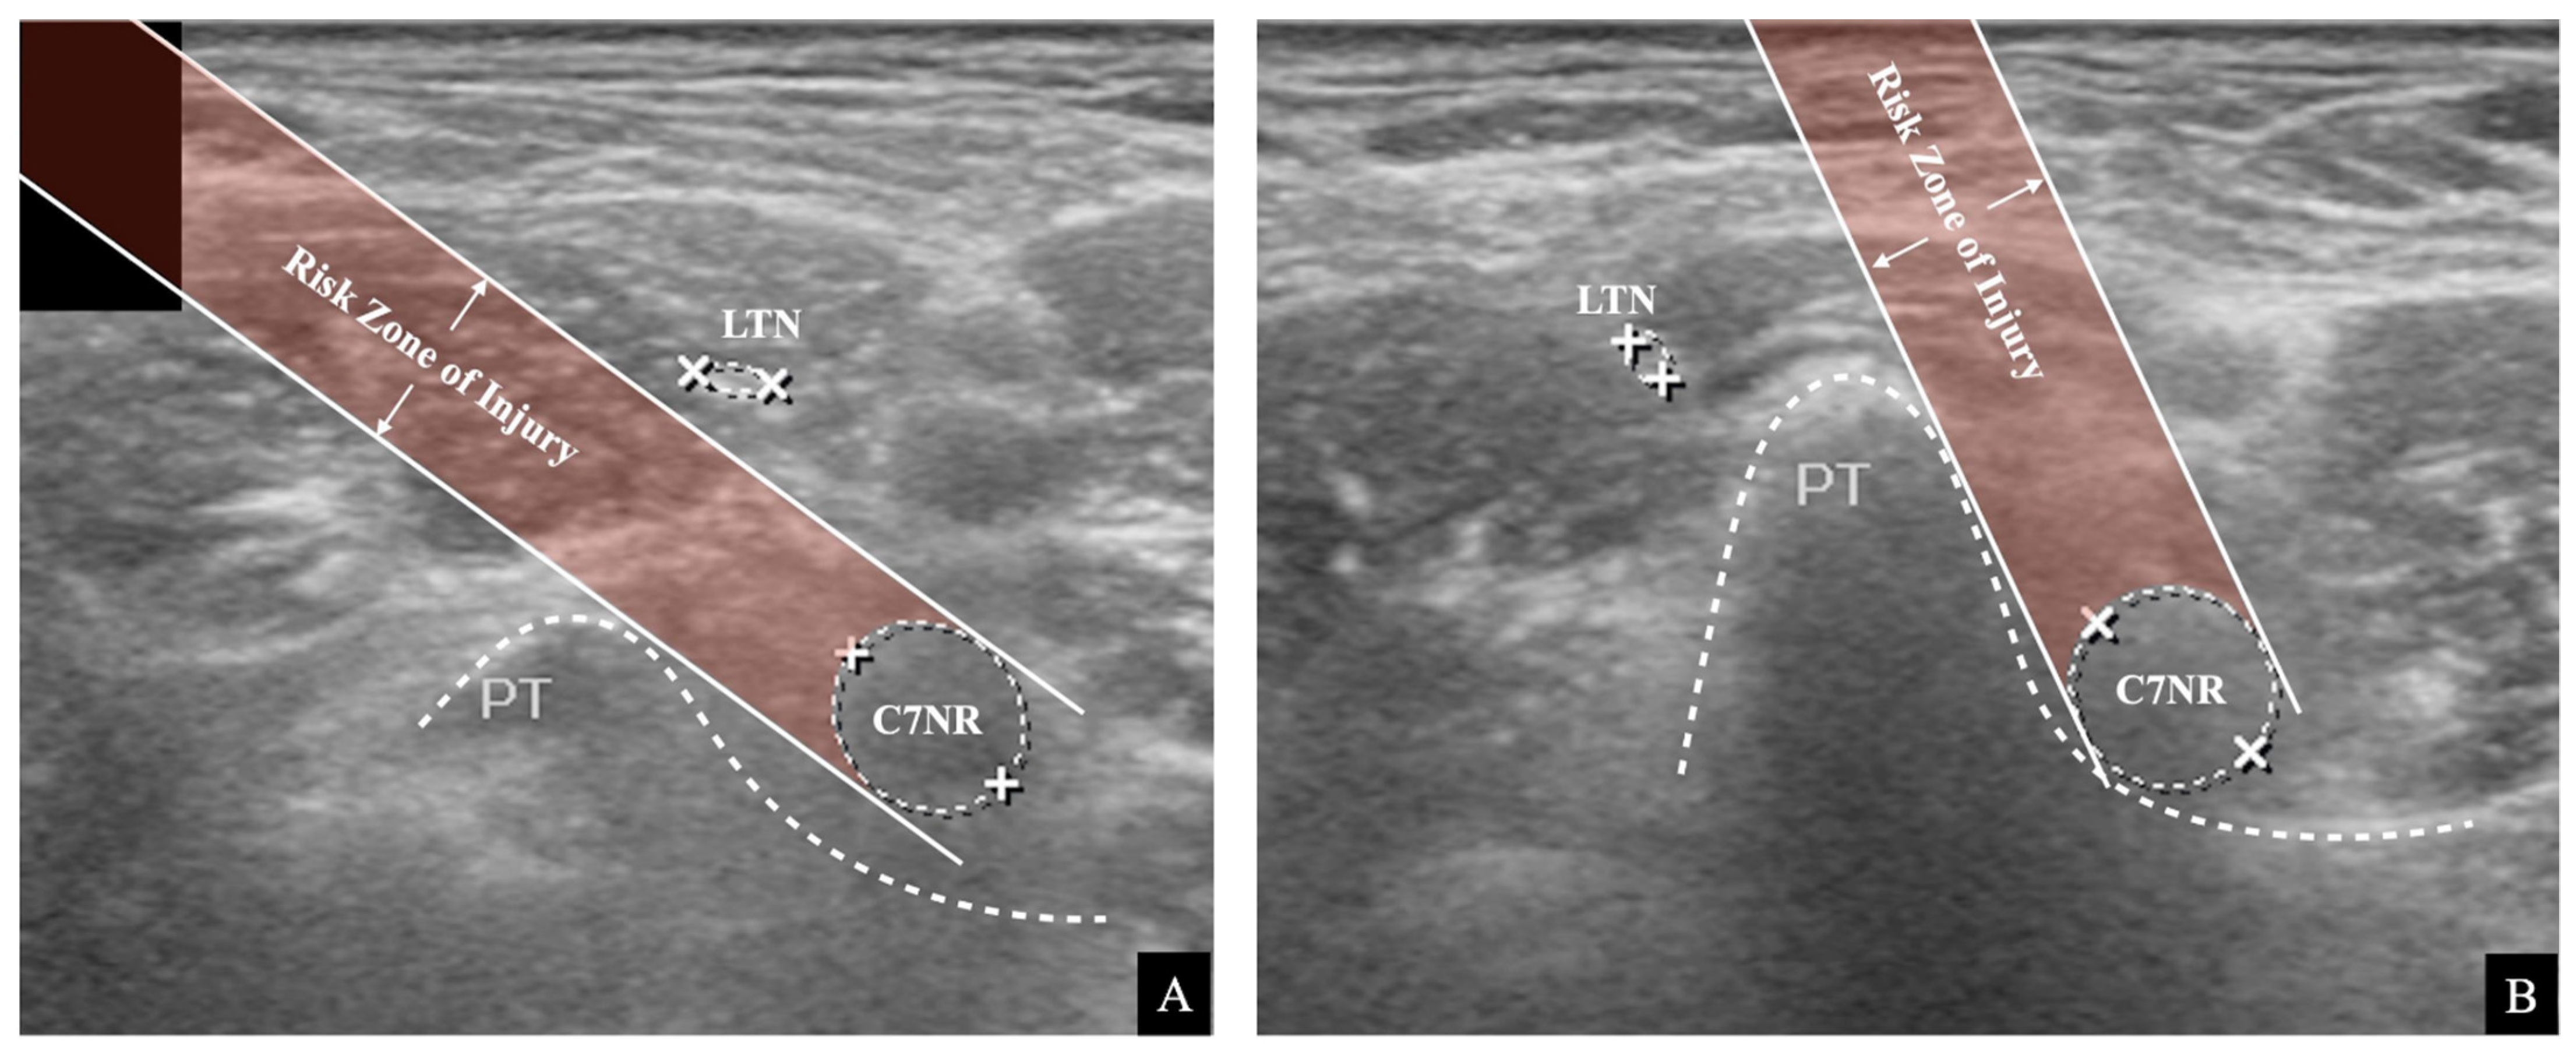

indicates that it was outside the risk area in the simulated risk analysis. The LTN’s mean location and locational area estimated by the mean ± standard deviation (SD) are presented. The painted area indicates that the needle’s trajectory is expected to be associated with a high risk of LTN injury.